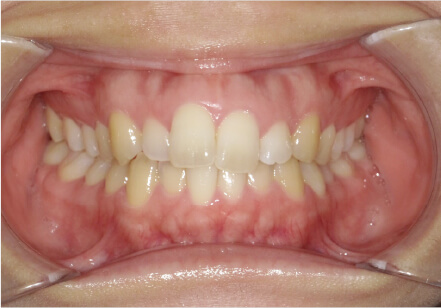

叢生の症例

19歳

女性

相談内容

上の前歯が出っ歯、下の前歯がガタガタ

カウンセリング・診断結果

抜歯承諾、IPR承諾、アタッチメント承諾、ミニインプラント承諾、アレルギー有・叢生(凸凹)

治療内容・方法

全顎アライナー矯正 抜歯予定だったが抜歯リスク高いため抜歯なしでIPR量を増やす

術後の経過・現在の様子

クリアライナー

治療のリスク

痛み・歯根吸収・歯肉退縮・虫歯・後戻り

費用・治療期間

880,000円、1年5ヶ月